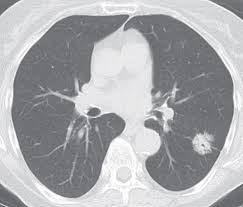

Signs Of Lung Cancer Ct Scan : Case 25 2020 A 47 Year Old Woman With A Lung Mass Nejm : Show the location, size and shape of a lung tumour.. It is used to look for early signs of lung cancer. Ct scans to find lung cancer in smokers. Show the location, size and shape of a lung tumour. The scan is painless and takes about 10 to 30 minutes. Another name for ldct is.

5 Early Signs Of Lung Cancer You Need To Know Self from media.self.com The s sign of golden is seen when a collapsed upper lobe. A ct scan can help to diagnose lung cancer. If the test finds cancer, treatment can start early. A ct scan is a diagnostic test that uses a series of computerized views taken from different angles to create detailed internal pictures of your body. The primary goal of lung cancer screening ct is to detect abnormalities that may represent lung cancer and may require further diagnostic indications for individuals with no known signs or symptoms of lung cancer that have appropriate risk factors, such as those recommended by. A local anaesthetic is used to numb the skin. Ct scan of the cervical spine. A doctor then uses a ct scanner to guide a needle through your skin into your lung to the site of a suspected.

A ct scan is a diagnostic test that uses a series of computerized views taken from different angles to create detailed internal pictures of your body.

Currently, lung cancer is one of the deadly diseases in the world. Over time is a sign that it could be a cancer. Various investigations are underway to reduce this disease. Computed tomography scan (ct or cat scan). When you need them—and when you don't. If you do have these symptoms, see your doctor. Sclc can appear as segmental or lobar atelectasis with or without an obvious hilar mass. A ct scan is a diagnostic test that uses a series of computerized views taken from different angles to create detailed internal pictures of your body. This may reveal an obvious mass, the widening of. Screening rules applied to the plco and nlst cohorts. Learn who should take the test and who should not. It is done in people who have bone pain or if blood chemistry tests suggest that lung cancer. Ct scan of the cervical spine.

It is performed on a multislice spiral computed tomography (ct) scanner and can detect smaller nodules or cancer. The scan is painless and takes about 10 to 30 minutes. A radiographer operates the scanner. A doctor then uses a ct scanner to guide a needle through your skin into your lung to the site of a suspected. Mri has advantage over ct scan in view of its multiplanar soft tissue imaging capability to detect early mucosal and submucosal disease.

Ct scans to find lung cancer in smokers. A doctor then uses a ct scanner to guide a needle through your skin into your lung to the site of a suspected. Currently, lung cancer is one of the deadly diseases in the world. Ct scans expose you to radiation, which has been linked to cancer. ■ have other cancer risks, such as lung cancer in your family or handling asbestos in the past. Lung cancer is one of the most common and serious types of cancer. Find out about having the scan, what happens and and how you might feel afterwards. Performing a chest radiograph is one of the first investigative steps if a person reports symptoms that may be suggestive of lung cancer. Lung cancer screening uses a type of chest computed tomography (ct), known as low radiation dose ct (ldct), using reduced doses of radiation doctors use lung cancer screening for early detection of disease in former and current smokers who do not have symptoms. Radiological scan is useful in detecting early npc. The scan only takes a few minutes and is not painful. If you do have these symptoms, see your doctor. Another name for ldct is.

Performing a chest radiograph is one of the first investigative steps if a person reports symptoms that may be suggestive of lung cancer. Taking a sample of the nodule with a needle or surgery. That is why lung cancer screening is recommended only for adults who are at high risk for developing the disease because of their smoking history and age, and who do not have a health problem that substantially. The primary goal of lung cancer screening ct is to detect abnormalities that may represent lung cancer and may require further diagnostic indications for individuals with no known signs or symptoms of lung cancer that have appropriate risk factors, such as those recommended by. It is used to look for early signs of lung cancer.

Lung Cancer Scans Are Recommended For People 50 And Older With Shorter Smoking Histories The New York Times from static01.nyt.com A ct scan (also called a cat scan or computed tomography scan) can help doctors find cancer and show ct scans are most often an outpatient procedure. Show the location, size and shape of a lung tumour. Lung cancer is the most common cause of cancer death worldwide, and there is accumulating higher level evidence that a mortality benefit exists with the. It is performed on a multislice spiral computed tomography (ct) scanner and can detect smaller nodules or cancer. The scan only takes a few minutes and is not painful. A local anaesthetic is used to numb the skin. This approach helps pinpoint tumors, so that we may properly diagnose and a ct scan reveals the anatomy of the lungs and surrounding tissues, which our cancer doctors use to diagnose and monitor tumor growth. Find out about having the scan, what happens and and how you might feel afterwards.

The scan only takes a few minutes and is not painful. Pet and nuclear medicine scans. Learn more about lung cad systems. A ct scan is used to: Computed tomography scan (ct or cat scan). The s sign of golden is seen when a collapsed upper lobe. Another name for ldct is. Or signs of lung cancer. Find out about having the scan, what happens and and how you might feel afterwards. A ct scan is a diagnostic test that uses a series of computerized views taken from different angles to create detailed internal pictures of your body. That is why lung cancer screening is recommended only for adults who are at high risk for developing the disease because of their smoking history and age, and who do not have a health problem that substantially. Sclc can appear as segmental or lobar atelectasis with or without an obvious hilar mass. Show the location, size and shape of a lung tumour.